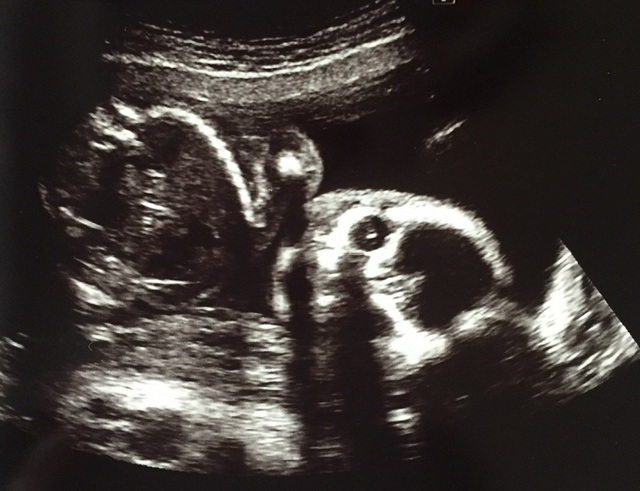

21週0日(21w0d・男の子))|ai*c さん(27歳)

エコー写真撮影時のエピソード:

エコー写真は基本いつも顔が下を向いていて見せてくれませんでした。 今回のエコーの写真の時も最初は下を向いていて見れないねーと話してたらこっちを見てくれました。その時に助産師さんがパシャリ! 初めての正面でした。